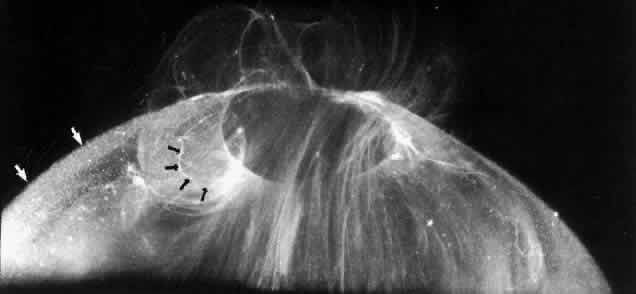

Researchers88–91have used these techniques to study human vitreous structure. Within the adult human vitreous there are fine, parallel fibers coursing in an anteroposterior direction, as shown in Figs. 4B AND C, 5, and 6. The fibers attach into the vitreous base (see Figs. 4H and 5) where they splay out anterior and posterior to the ora serrata. As the peripheral fibers course posteriorly they are circumferential with the vitreous cortex, while central fibers “undulate” in a configuration parallel with Cloquet's canal.6 The fibers are continuous and do not branch. Posteriorly, these fibers attach into the vitreous cortex (see Fig. 4E and F), but not the internal limiting lamina of the retina.

Fig. 5. Posterior and central vitreous of a 59-year-old man. Fibers course anteroposteriorly in the center of the corpus vitreous and enter the retrocortical space through the premacular region of the vitreous cortex (to the top at the center). Within the cortex are many small “dots” that scatter light intensely (white arrows). The larger, irregular dots are debris. The smaller dots are hyalocytes. (Sebag J: The Vitreous--Structure, Function and Pathobiology. New York, Springer-Verlag, 1989)

Fig. 6. Vitreous structure in a 58-year-old woman. Fibers course anteroposteriorly in the central and peripheral vitreous. Posteriorly, fibers orient to the premacular region (top). Anteriorly, the fibers “splay out” to insert into the vitreous base (bottom right). (Sebag J: The Vitreous--Structure, Function and Pathobiology. New York, Springer-Verlag, 1989)

Fig. 4. Human vitreous structure is visualized by darkfield slit microscopy. All photographs are oriented with the anterior segment below and the posterior pole above. Photographs are sequential, beginning in the upper left hand corner and moving left to right. A. Posterior vitreous in the left eye of a 52-year-old man. The corpus vitreous is enclosed by the vitreous cortex. There is a hole in the prepapillary (small, to the left) vitreous cortex. B. Posterior vitreous in a 57-year-old man. A large bundle of prominent fibers is seen coursing anteroposteriorly and entering the retrohyaloid space through the premacular vitreous cortex. C. Same view as B at higher magnification. D. Posterior vitreous in the right eye of a 53-year-old woman. There is posterior extrusion of vitreous out the prepapillary hole (to the right) and premacular (large extrusion to the left) vitreous cortex. Fibers course anteroposteriorly in the central vitreous and out into the retrocortical (formerly preretinal, before dissection) space. E. Horizontal optical section of the same specimen as D at a different level. A large fiber courses posteriorly from the central vitreous and inserts into the premacular vitreous cortex. F. Same view as E at higher magnification. The large fiber has a curvilinear appearance because of traction by vitreous extruding into the retrocortical space. However, because of its attachment to the posterior vitreous cortex the fiber arcs back to its point of insertion. G. Anterior and central vitreous in a 33-year-old woman. Cloquet's canal is seen forming the retrolental space of Berger. H. Anterior and peripheral vitreous in a 57-year-old man. The specimen is tilted forward to enable visualization of the posterior aspect of the lens and the peripheral anterior vitreous. Behind and to the right of the lens there are fibers coursing anteroposteriorly that insert into the vitreous base. These fibers “splay out” to insert anterior and posterior to the ora serrata. (A, E, and F: Sebag J, Balazs EA: Pathogenesis of cystoid macular edema: An anatomic consideration of vitreoretinal adhesions. Surv Ophthalmol 28[suppl]:493, 1984; B and C: Sebag J, Balazs EA: Morphology and ultrastructure of human vitreous fibers. Invest Ophthalmol Vis Sci 30:187, 1989)